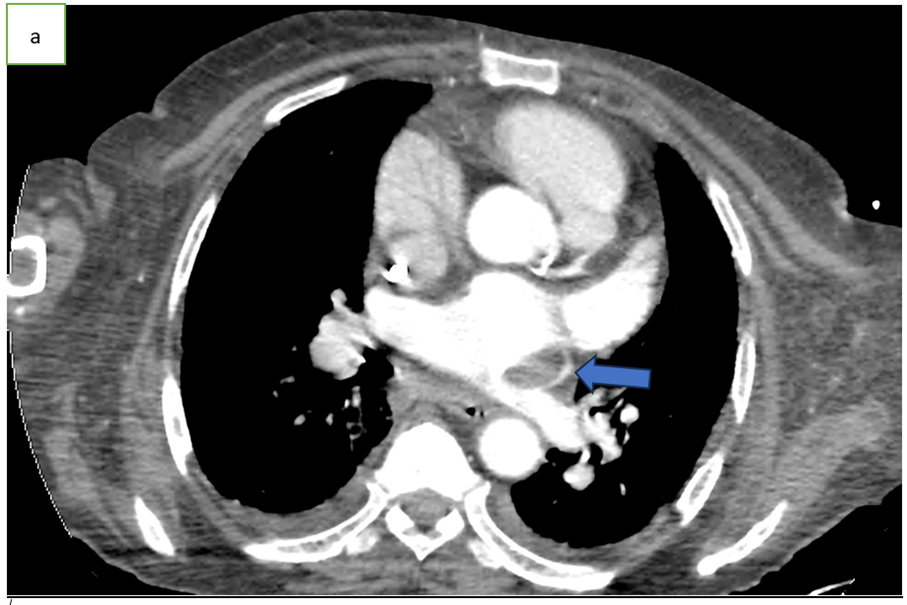

Figure 1: Axial CT scan angiography (a), coronal (b) and sagittal (c) reconstruction, showing an endoluminal thrombi in the pulmonary vein (arrow).

Chest CT angiography is the preferred imaging method, typically showing a well-defined, hypodense endoluminal thrombus in a pulmonary vein [1,3], outlined by contrast but not enhancing after injection [1].